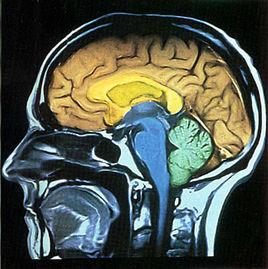

人生的某些經歷很難忘卻,科學家利用大腦成像技術設法弄清楚創造記憶和儲存記憶的機械反映。發現大腦灰質內部的海馬體能充當記憶儲存箱的功能。但是這個儲存區域的分辨能力並不強。對相同的大腦區域的刺激,可以讓它產生真實的和虛假的記憶。為了把真實記憶從虛假記憶中脫離出來,研究人員提出根據背景回憶以加強記憶的方法,如果某些事情沒有真正發生過,就很難通過這種方法加強人腦對它的記憶。